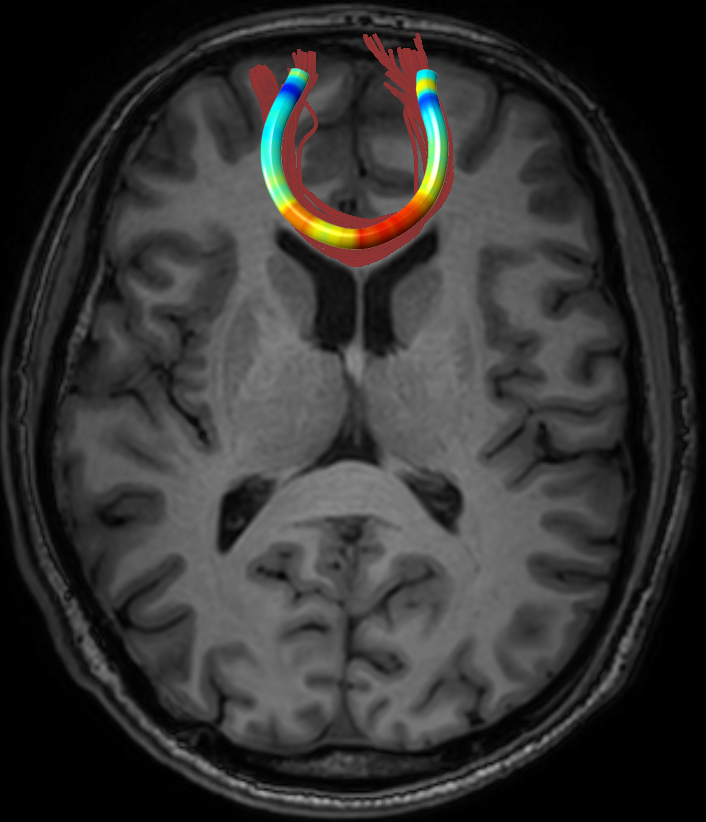

We performed pairwise comparison between two scans of a 32-year-old basketball player, diagnosed with mild occipital traumatic brain injury and frontal hemorrhage due to contrecoup impact, acquired one week and 6 months post-injury. The hemorrhagic lesion at the frontal right hemisphere of the player is no longer visible in the FLAIR image acquired 6 months after injury (Fig. 2a). Local differences between corresponding, longitudinal FA- and MD-FFDD profiles of the FMT (chosen due to its proximity to the lesion area) are shown in Fig. 2d. Figs. 2b-c present color-coded FMT to visually demonstrate these differences. Results show significant longitudinal variability at the right hemisphere part of the tract, corresponding to the lesion area, and relatively minor differences along the rest of the tract. These results should be considered as a proof of concept, validating the FFDD analysis results for the detection and localization of mTBI-related variabilities between fiber bundles.

| ONE WEEK | ![]() |

![]() |

FA-FFDD |

| 6 MONTHS | ![]() |

MD-FFDD |

| (a) FLAIR | (b) FA-FFDD | (c) MD-FFDD | (d) Local Differences |